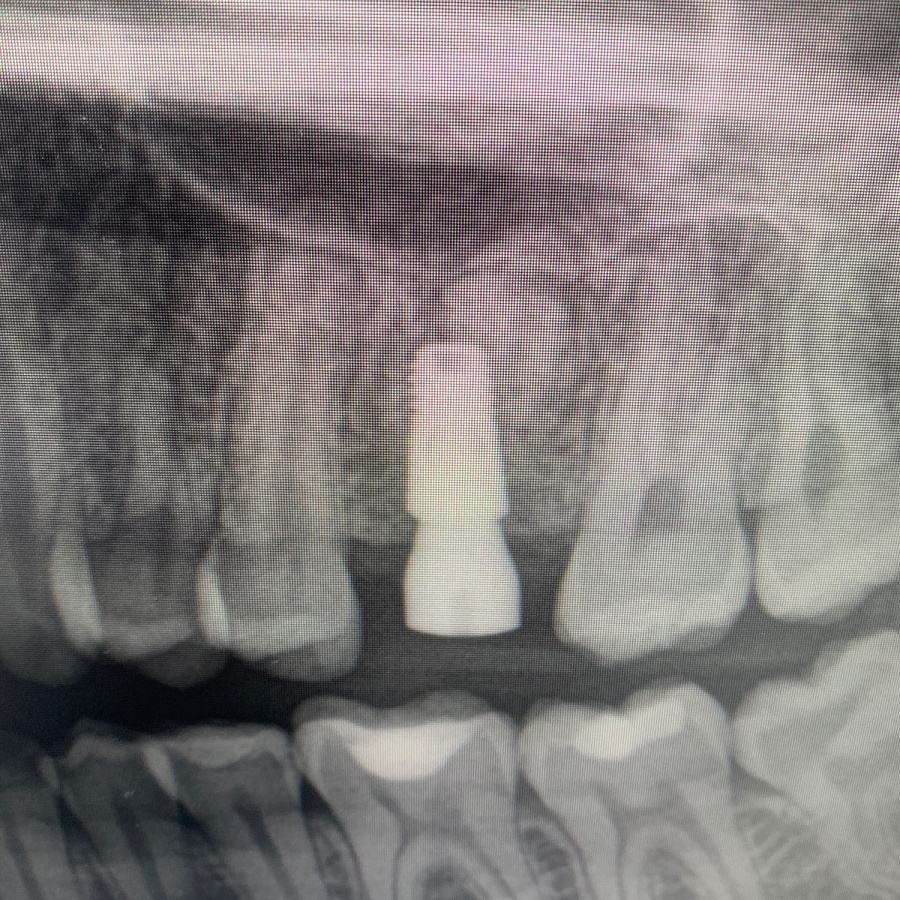

Пациент, 22 года. Обратилась к терапевту с жалобами на дискомфорт при накусывании на зуб в верхней челюсти слева.

В ходе эндодонтической диагностики доктор обнаружил трещину в корне зуба.

Сохранить или вылечить зуб невозможно, поэтому было рекомендовано удаление зуба с последующей имплантацией.

После удаления таких зубов и извлечения кисты, в кости остаётся большой дефект. Поэтому сделать одномоментную имплантацию зуба, т.е. удаление и имплантацию за один приём невозможно. В таких случаях необходимы дополнительные хирургические манипуляции по подсадке искусственной кости, чтобы сохранить объём костной ткани для последующего протезирования.

Через 6 месяцев после подсадки кости - контрольный снимок и установка зубного имплантата.